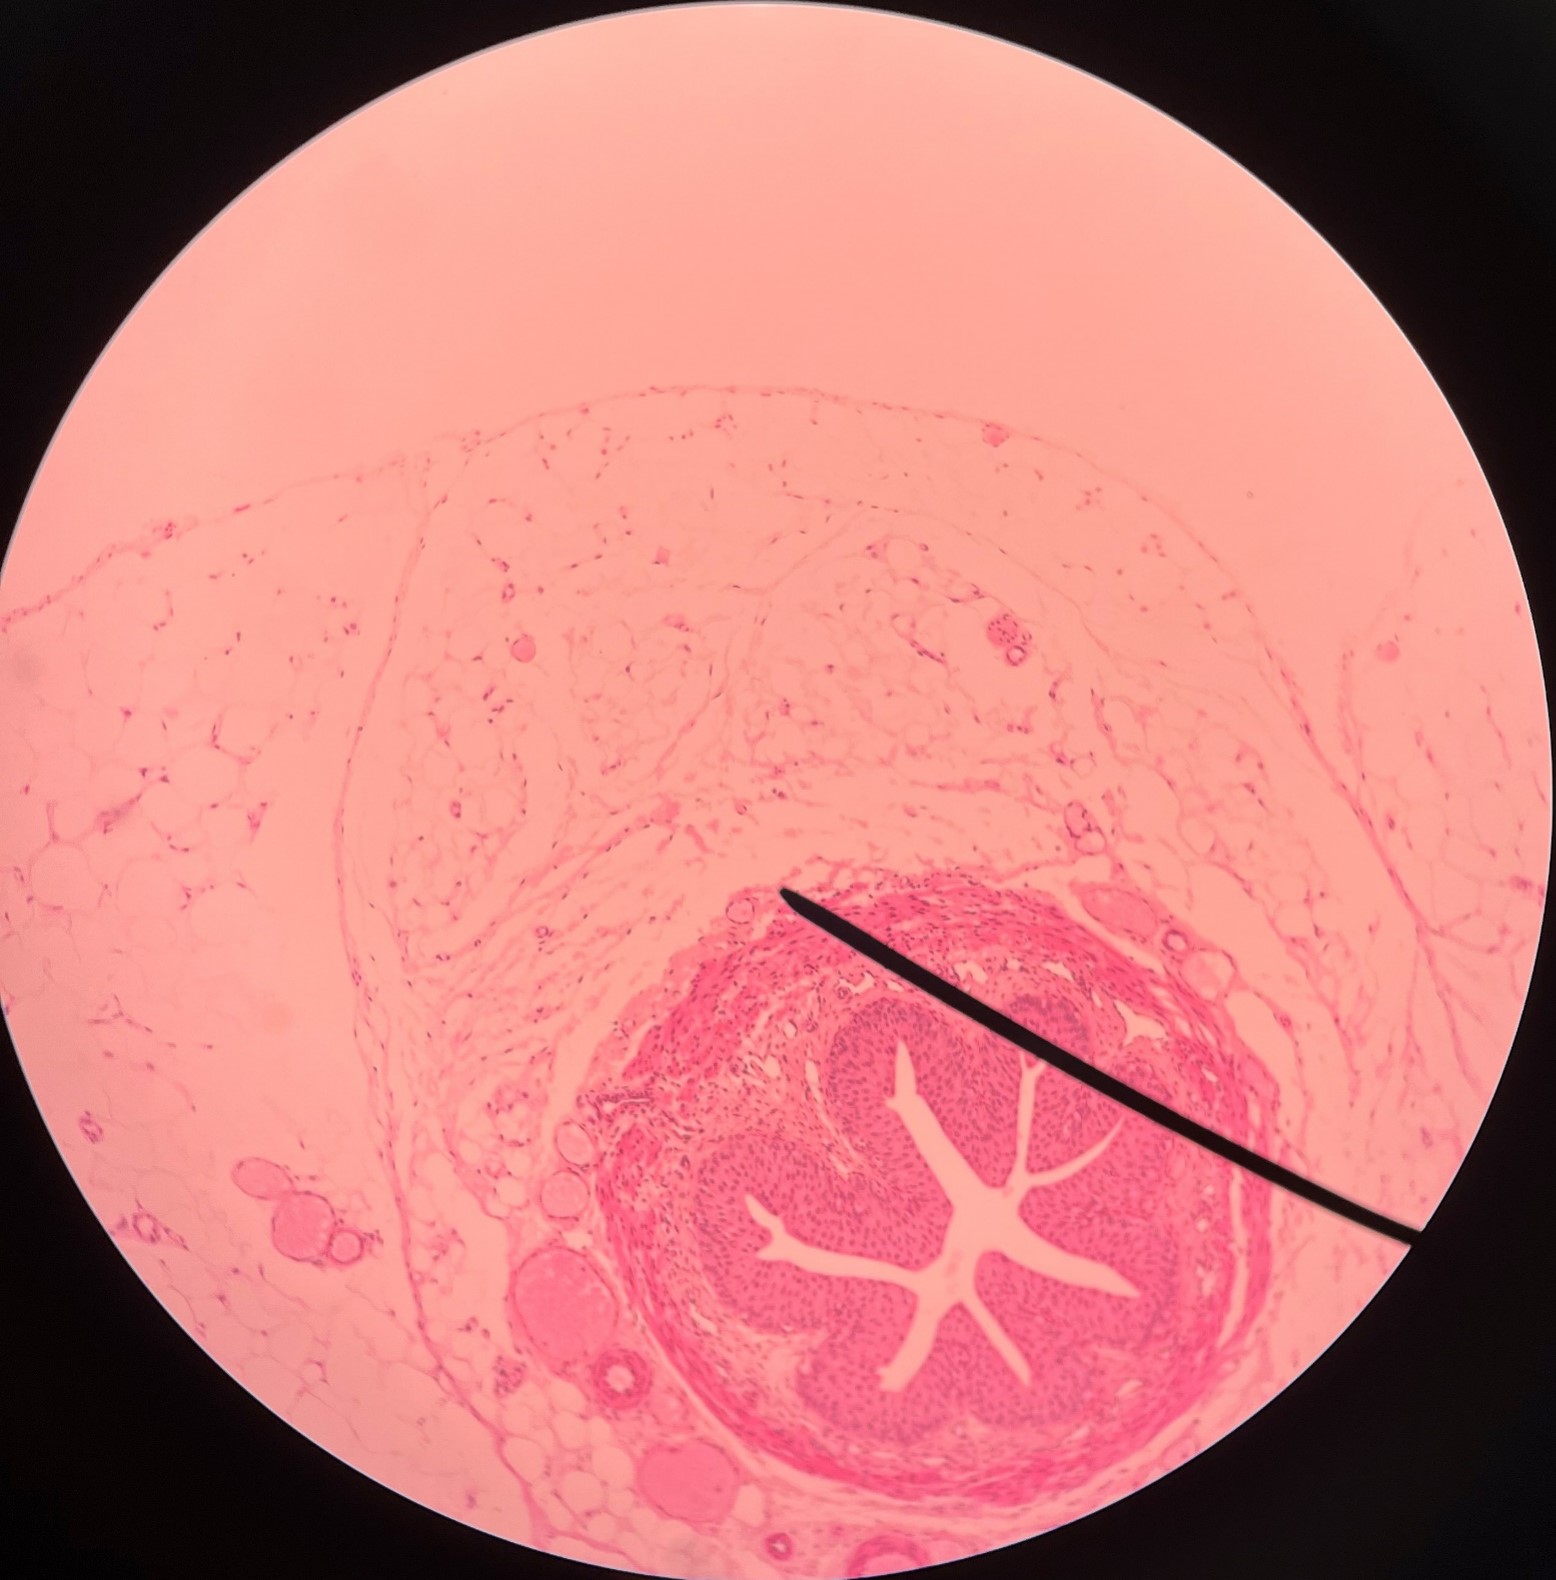

adventitia

• Slide histology of the ureter.

• The outermost layer of the ureter.

• Composed of connective tissue.

• Superficial to the circular layer of the muscularis.

circular layer of muscularis

• Slide histology of the ureter.

• A smooth muscle layer of the ureter.

• Superficial to the longitudinal layer of the muscularis and deep to the adventitia.

longitudinal layer of muscularis

• Slide histology of the ureter.

• A smooth muscle layer of the ureter.

• Superficial to the mucosa and deep to the circular layer of the muscularis.

mucosa

• Slide histology of the ureter.

• The innermost layer of the ureter.

• Composed of urothelium.

• Faces the lumen of the ureter and is deep to the longitudinal layer of the muscularis.